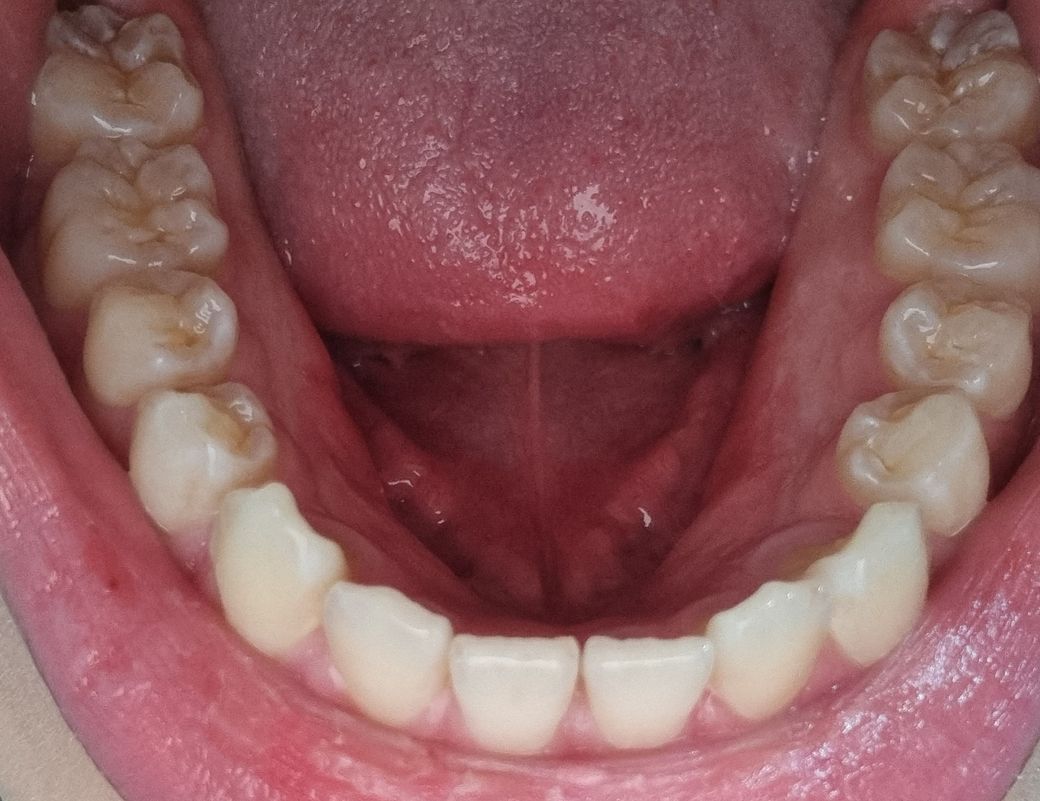

지금 제 치아가 치료가 필요한 상태인가요?

최근 치아 상태를 한번 확인해봤는데 어금니의 씹는 부분이 많이 녹고 금이 깊어져있는 상태인 것 같습니다. 지금 치아 상태가 어느정도인가요? 당장 치과에 가서 치료가 필요한 수준인가요?

• 1번 째 사진

일단 사진상으로는 괜찮아보이나, 엑스레이등을 찍어봤을 때

충치나 다른 문제점이 나올 수 있으니 치과가서 검진 받아보세요^^

사진상으로 보면 크게 문제가 되는건 없는거 같습니다. 정확한건 치과에 가셔서 엑스레이를 찍어보시는게 좋을것같습니다.

현재 사진에서 나온 부위에는 특별히 치료를 해야할 정도의 치아는 없습니다. 다만 촬영된 부위가 극히 좁고 치아 인접면 그리고 다양한 부위를 볼 수 없어 진단에 한계는 있습니다. 정확한 진단을 위해서는 치과 방문 후 x-ray 등의 평가가 필요합니다.

치아가 마모되어있는 부분들이 상당히 관찰이 되긴하지만 바로 치료를 받을 정도는 아닌 것 같습니다.

해당 부위는 치아에 구조입니다. 사진으로만 봤을 경우에는 크게 문제가 없는 것으로 보입니다 자세한 확인을 위해서 치과에서 진료를 받아보는 것을 권유드립니다

어금니 부위는 금이갔다기 보다는 원래 해부학적인 모양입니다 치아의 소와열구, 그루브이며 효율적인 음식물 저작에 도움을 주는 구조들입니다